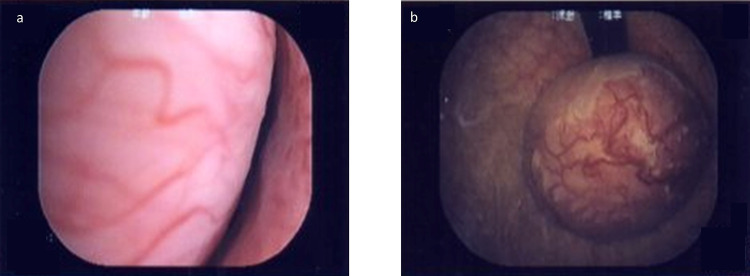

Case presentation: A 53-year-old woman presented to a local clinic with frequent urination and dysuria and was diagnosed with acute cystitis. Her symptoms temporarily improved after taking oral antibiotics, but then flared up repeatedly. Contrast-enhanced computed tomography showed a bladder neck leiomyoma and multiple uterine fibroids. Her body mass index was 27.0 kg/m2. The patient successfully underwent transurethral resection of the tumor. The histopathological diagnosis was bladder leiomyoma.